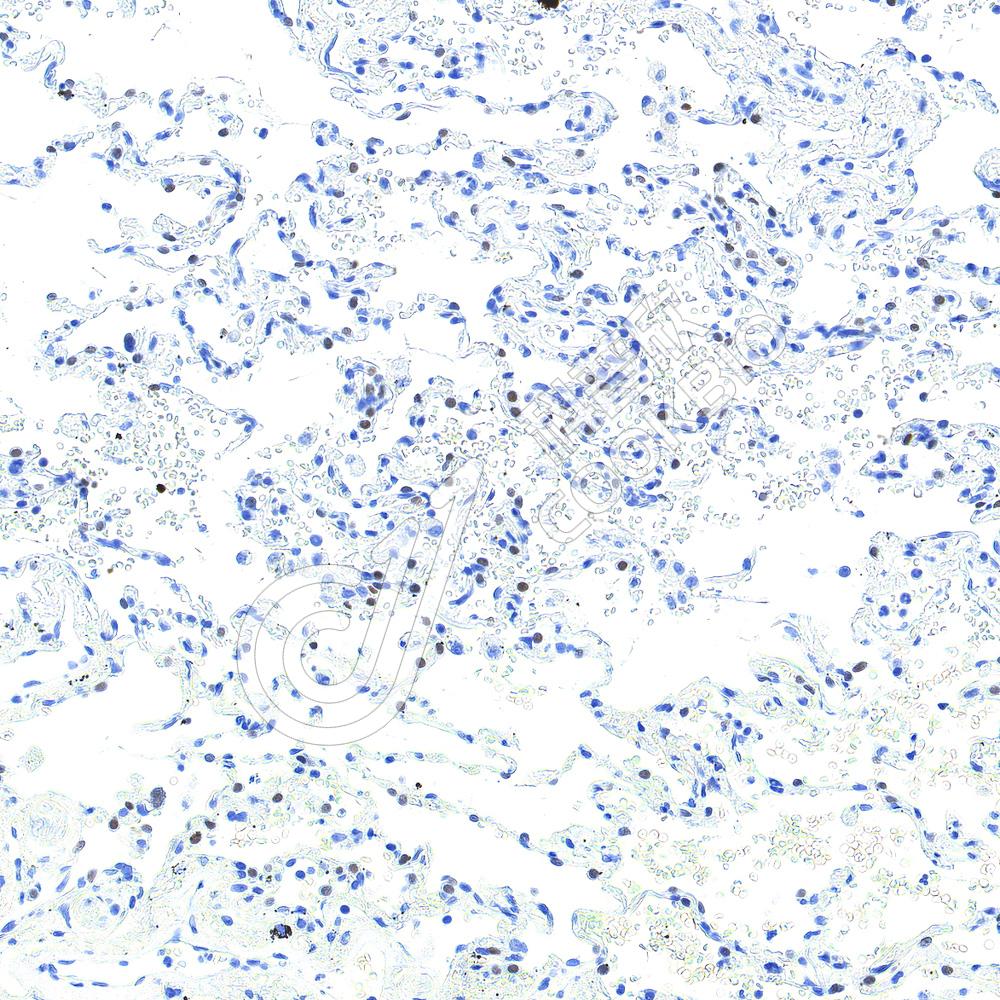

IHC检测Ki67蛋白(货号 K5450069).

样品: 人扁桃体, 4%多聚甲醛 (货号KSG1101) 固定12-24小时.

抗原修复: 柠檬酸抗原修复液(干粉, pH 6.0) (KSG1201), 高压锅均匀喷气计时2分钟.

—抗: 1: 2000稀释, 4℃ 孵育过夜.

二抗: S-vision免疫组化多聚二抗(山羊抗小鼠), 即用型(货号KB3903), 室温孵育20分钟.